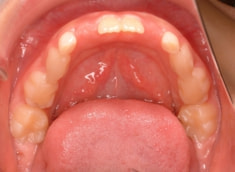

治療後(1年7ヶ月後)